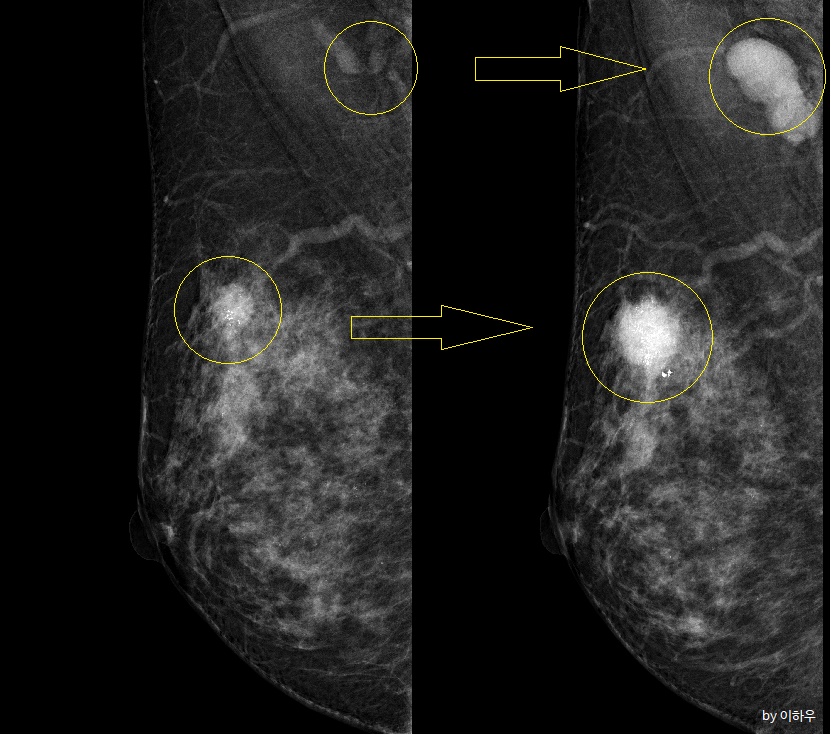

석회화는 거대 석회화(Macrocalcifications)와 미세 석회화(Microcalcifications)로 나뉩니다. 일반적으로 0.5mm 이하의 석회화를 미세석회화라고 합니다. 그보다 크면 거대 석회화라고 생각하시면 될 것 같습니다. 대부분의 거대 석회화는 양성질환입니다. 암과는 관련이 거의 없습니다. 문제는 미세 석회화입니다. 미세석회화라고 하여서 꼭 암과 관련이 있는 것은 아니지만, 그 수가 많거나 어떤 특정한 패턴을 보이는 경우에는 유방암을 의심하게 되고 추가 검사를 시행하게 됩니다.

가장 중요한 것은 유방 촬영상 석회화가 보일 때입니다. 개인적으로도 석회화는 긴장하게 하는 단어입니다. 석회화가 보이게 되면 크게 3가지의 경우로 나누어서 진료를 하게 됩니다.